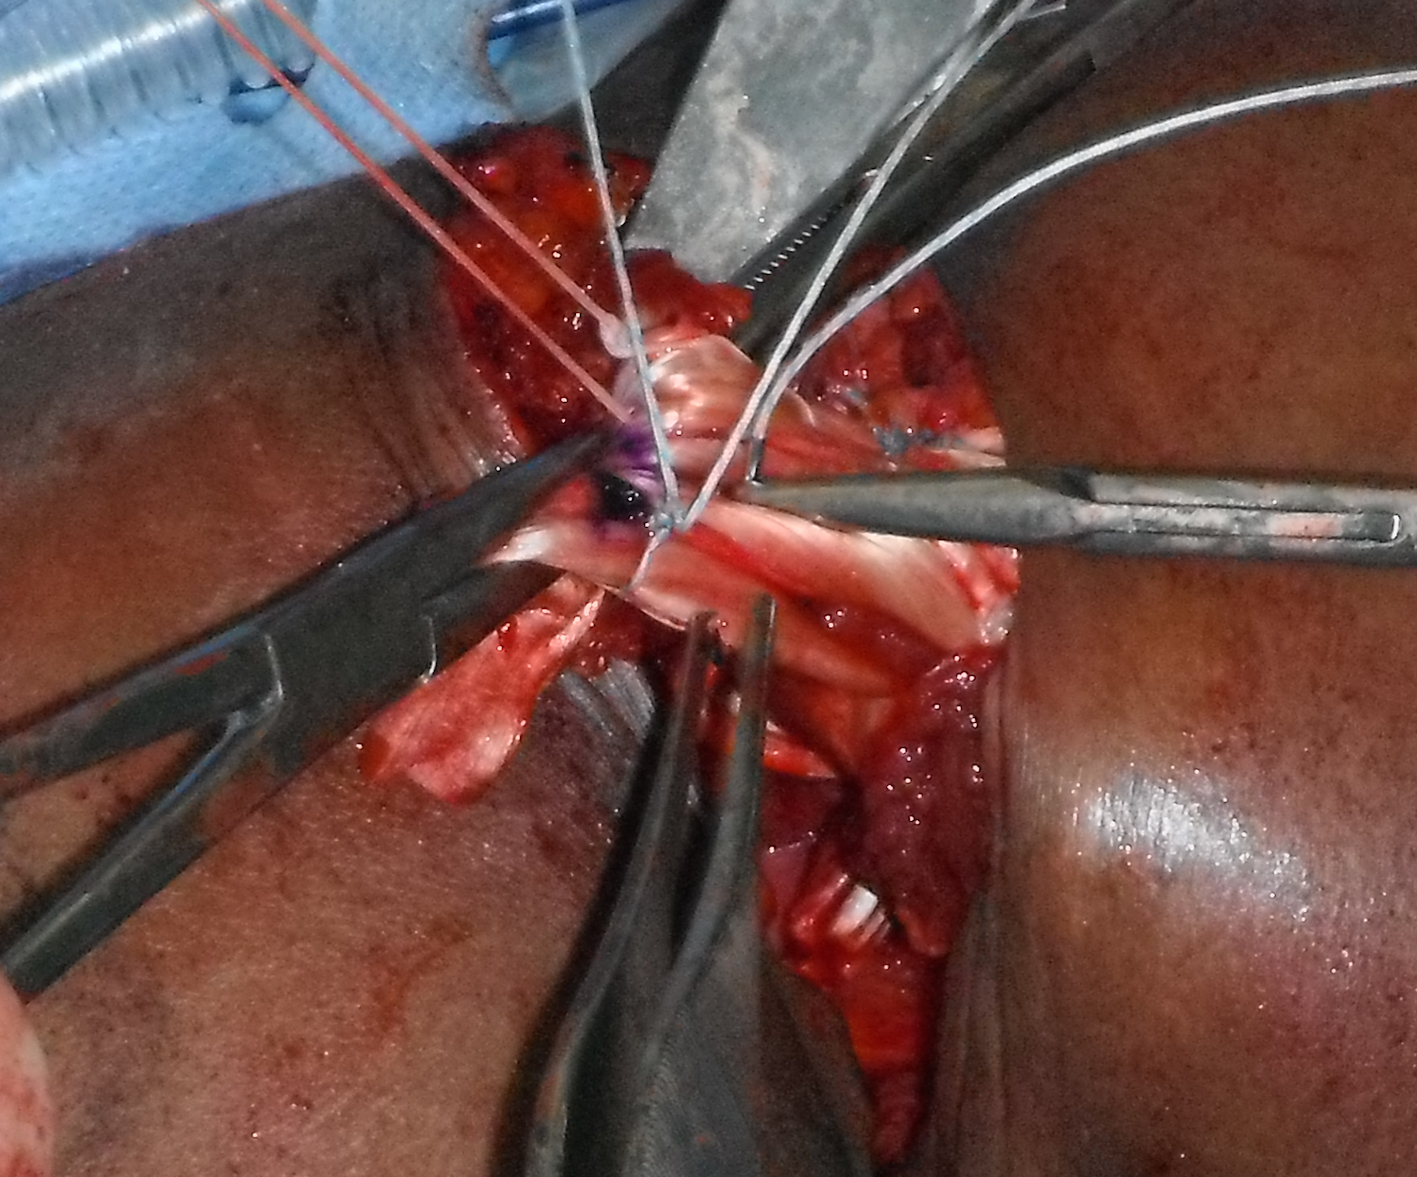

Pect Major Reconstruction 14 Suturing allograftPec Major Reconstruction 3

Right shoulder: allograft has been passed through sternal and clavicular muscle bellies and is being sutured back onto itself